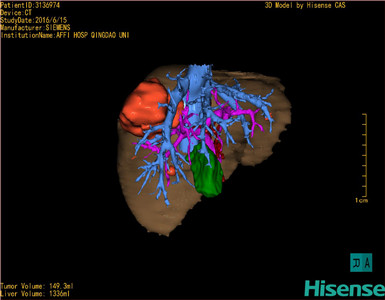

将0.625mm双源薄层CT资料的静脉期和动脉期Dicom格式文件导入海信CAS系统。

通过调节窗宽窗位调整CT序号,对肿瘤,肝实质,胆囊,下腔静脉,肿瘤,肝动脉、门静脉及肝静脉等进行三维重建;系统自动计算肿瘤体积和肝脏体积。

模拟手术操作,自动计算切除肿瘤体积。肝脏体积为1336ml,肿瘤体积为149.3ml,肿瘤体积为肝脏体积的11.2%,通过比对50-60岁正常肝脏体积为1330.41±329.13 ml,通过术前模拟手术,精准判断切除后剩余肝脏体积能耐受,避免肝衰竭发生。

术前三维重建:重建图片